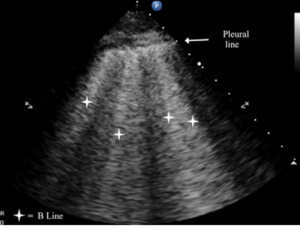

B-lines are small, well-defined comet tail-like artifacts arising perpendicularly from the pleural line (Figure 2a). During respiration, these lines move along the pleural line and may erase A-lines. One or two B-lines may be seen per intercostal space in 30% of healthy individuals, particularly in dependent regions of the lung20 B-lines indicate filling of the interstitial space and are often observed in pulmonary edema.21

Typical patterns of ultrasound imaging are seen at various scanning points during the diagnosis of pneumonia. From the anterior perspective, typical C-lines identified by a curvilinear aspect of the pleural line are caused by adjacent consolidated tissue; as in pneumonia, the alveoli are filled with fluid (Figure 3). The non-aerated lung tissue is thus readily transverse by ultrasound beams, producing an image comparable with liver tissue.7,18

Nearly all consolidations touch the pleural line. As a result of gravity, consolidation usually appears first at the posterior-lateral point. By looking for air Bronchogram or the shred sign, pneumonia can be further analyzed. This is caused by the reflection of ultrasound beams in air-filled bronchi surrounded by consolidated tissue. The shred sign appears when the border between aerated and consolidated lung is not clearly defined.23